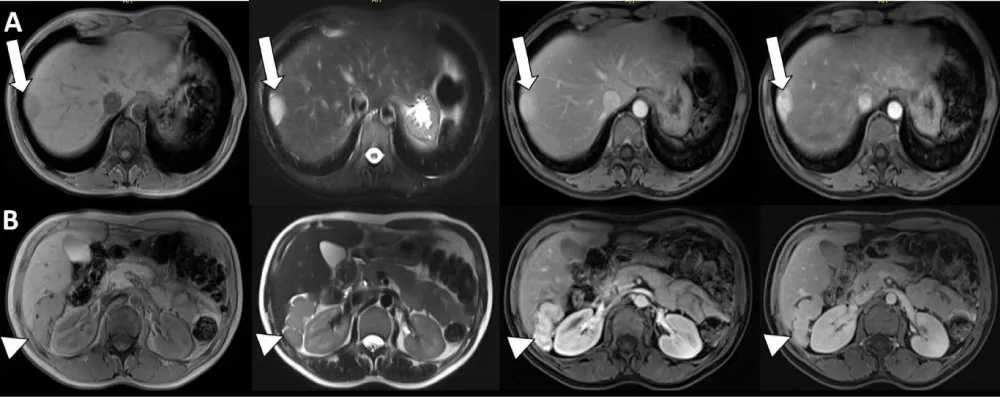

A 41-year-old woman with a history of abdominal pain was referred to ultrasonography (US). US was negative and computerized tomography (CT) was performed for further investigation. CT images disclosed the absent of spleen and a well-defined hypodense lesion compared to the liver, located near the liver capsule with a maximum diameter of 22 mm in the segment 8. In addition, multiple nodular formations were seen near the segment 6 of the liver. During the portal phase, the lesions were hyperdens compared to the liver. On MRI imaging, the lesions were hypointense on T1-weighted images and hyperintense on T2-weighted images. After contrast media administration (Gd+), all lesions showed heterogeneous contrast enhancement on the arterial phase, and homogeneous enhancement on the portal phase images (Figure 1). Peritoneal carcinomatosis was suspected but the patient had no complaints of fever, night sweats or weight loss, which suggests malignancy. Her history included splenectomy 20 years previously due to the traumatic rupture of the spleen during an accident. She went on to have 99mTc-labeled heat-damaged red blood cell (RBC) scintigraphy because of prior splenectomy. One gr of stannous ion (Sn+2) in the form of pyrophosphate was injected intravenously to the patient. 20 min later, a blood sample (approximately 8 cc) was obtained, 20 mCi of NaTc99mO4 was added, the sample was incubated at room temperature for 20 min then the sample was re-injected to the patient. Planar and hybrid single photon emission tomography/computed tomography images (SPECT/CT) were obtained. Planar images showed suspicious visual moderate activity uptake in the right upper quadrant and mild activity uptake in the left upper quadrant of the abdomen (Figure 2A). Hybrid SPECT/CT images provided the accurate localisation of the lesions in the liver (Figure 2B,C, thick arrow) and the other mesenteric and peritoneal ones (in the Morrison’s pouch and left paracolic gutter - Figure 2B,C, arrow head and thin arrow, respectively). These lesions were unchanged for ≥ 5 months compared to prior exams and did not demonstrate any changes in a second MRI session which performed 5 months later. The diagnosis of intrahepatic and peritoneal splenosis was confirmed without invasive diagnostic techniques.